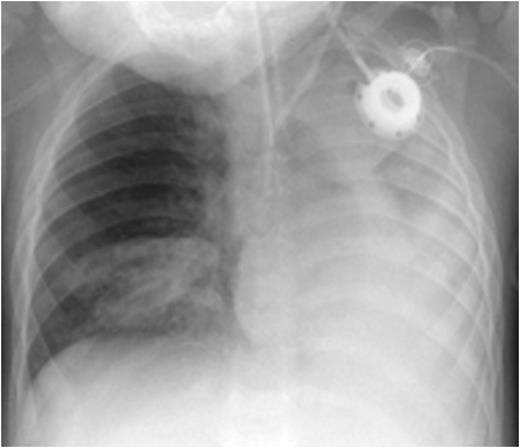

CXR before administration of plasminogen showed atelectasis of the left lung and of the right lower lobe (left panel). Six weeks after initiation of regulalar plasminogen substitution ventilation in both lungs had improved significantly (right panel)